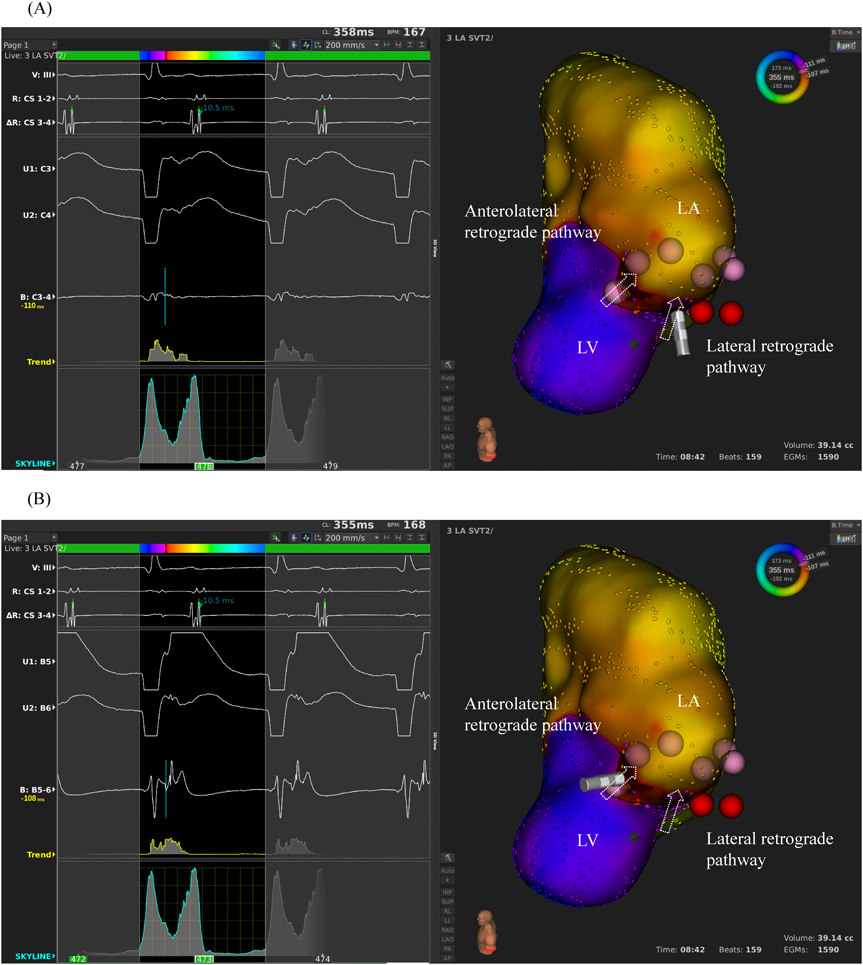

We used intracardiac echocardiography and a radiofrequency needle to perform transseptal puncture, and then inserted a long deflectable sheath (C MAP SYMMETRY; Century Medical, Inc. Tokyo, Japan) into the left atrium. During right ventricular pacing, we used the ORION™ high-density catheter (Boston Scientific) and the RHYTHMIA™ Mapping System to perform activation mapping, which demonstrated early left lateral activation followed by anterolateral atrial activation. Anterolateral activation, however, sometimes occurred as early as left lateral activation (Fig. 2A, 2B). The propagated waves collided at the distal portion of the left atrium through the mitral annulus. On activation mapping, the earliest atrial activation during AVRT coincided with that during right ventricular pacing (Fig. 3A, 3B; Supplementary Movie). Furthermore, 3D mapping showed that these earliest sites of atrial activation were 16.7 mm apart.

Fig. 3 Activation mapping during atrioventricular reciprocating tachycardia, which shows ventriculo-atrial conduction almost same to that through the anterolateral or the lateral retrograde pathway. (A) Left panel: the intracardiac electrocardiogram with retrograde conduction through the left lateral pathway. Right panel: the activation map, in which the tip of the catheter demonstrates the location of the left lateral pathway. The arrows indicate the lateral and the anterolateral retrograde pathways. (B) Left panel: the intracardiac electrocardiogram with retrograde conduction through the left anterolateral pathway. Right panel: the activation map, in which the tip of the catheter demonstrates the location of the left anterolateral pathway. The red and pink dots reflect radiofrequency application for the lateral and the anterolateral accessory pathways, respectively.

LA, left atrium; LV, left ventricle.